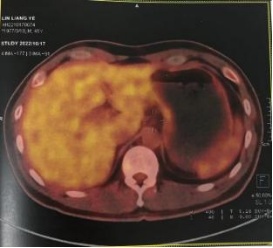

疗效评估:

2022-07至2022-10:

化疗方案:替吉奥60mg bid d1-14(q3w×4周期)

系统治疗后评估肿瘤退缩明显,经我院胃肠肿瘤MDT讨论并与患者及家属沟通后认为治疗有效,目前具备手术切除条件,拟再次手术治疗。